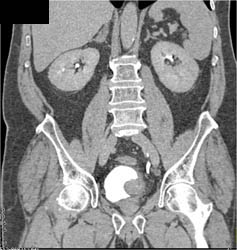

Bladder Cancer